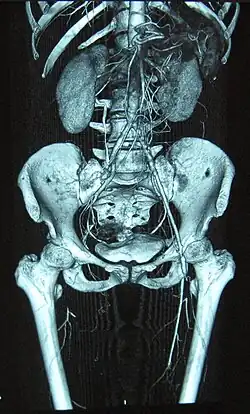

Complete occlusion of the right and stenosis of the left femoral artery as seen in a case of thromboangiitis obliterans

Angiograms of the upper and lower extremities can be helpful in making the diagnosis of Buerger's disease. In the proper clinical setting, certain angiographic findings are diagnostic of Buerger's. These findings include a "corkscrew" appearance of arteries that result from vascular damage, particularly the arteries in the region of the wrists and ankles. Collateral circulation gives "tree root" or "spider leg" appearance.[1] Angiograms may also show occlusions (blockages) or stenosis (narrowings) in multiple areas of both the arms and legs. Distal plethysmography also yields useful information about circulatory status in digits. To rule out other forms of vasculitis (by excluding involvement of vascular regions atypical for Buerger's), it is sometimes necessary to perform angiograms of other body regions (e.g., a mesenteric angiogram).